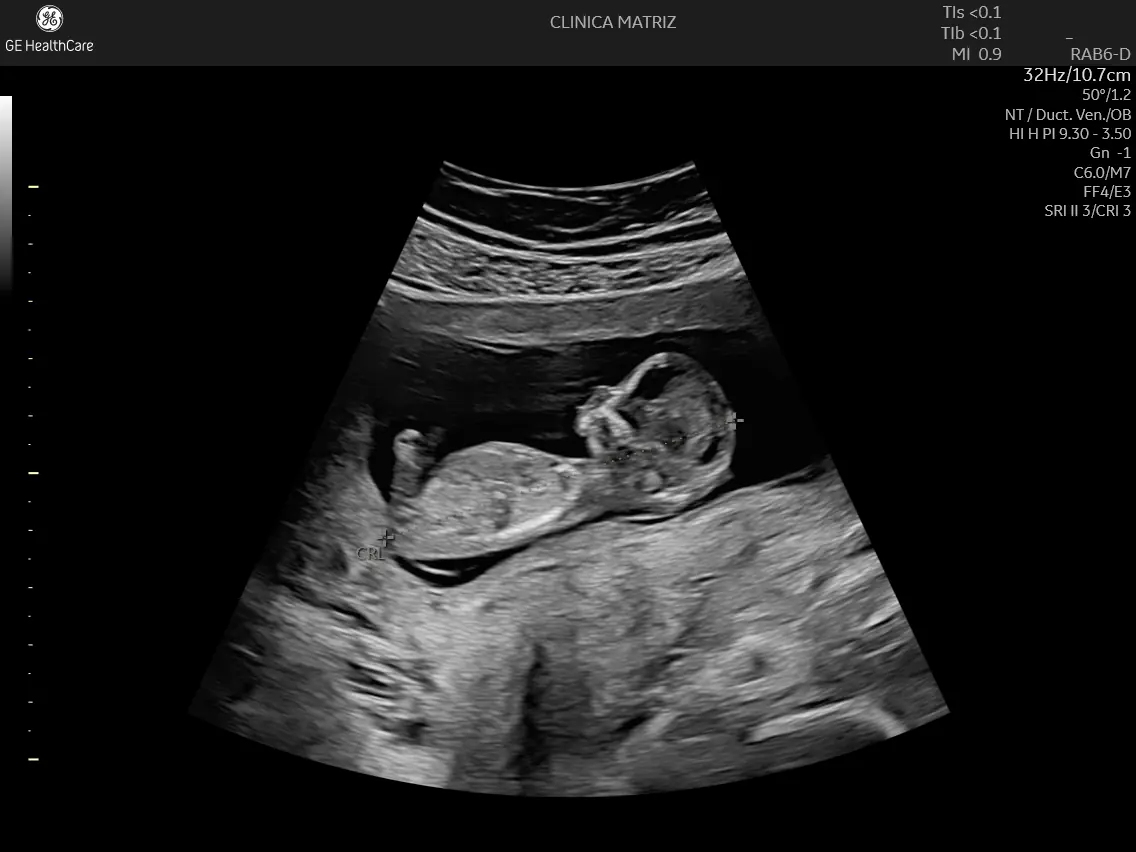

11–14 semanas: ecografia do 1.º trimestre (rastreio ecográfico)

Pode incluir a avaliação de marcadores ecográficos utilizados no rastreio do 1.º trimestre, de acordo com a indicação médica e os protocolos aplicáveis. Em termos gerais, esta fase permite:

- confirmar crescimento e vitalidade;

- datar com maior precisão;

- avaliar alguns marcadores associados ao risco de anomalias cromossómicas;

- detetar, em alguns casos, anomalias estruturais graves (nem sempre visíveis tão cedo).

Em muitas situações, esta ecografia integra-se no chamado rastreio pré-natal combinado (quando é associada a análises sanguíneas maternas), mas a necessidade e a forma de rastreio devem ser decididas contigo, de forma informada.